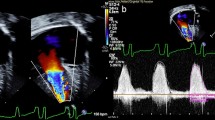

Piglets in Group 2b (n = 5) had PA banding at an average age of 31.8 ± 0.8 days and weight of 5.9 ± 0.2 kg. RV pressure increased from 21.6 ± 3.0 to 38.4 ± 7.5 mmHg (p = 0.003) after placing the band. All animals survived the banding procedure. At 51 ± 0 days post-banding piglets were prepared for the ASO. Piglets were 82.8 ± 0.8 days of age and 24.9 ± 2.8 kg at the time of the ASO. The arterial switch operation was completed in all five piglets. Three of the five piglets were successfully weaned from bypass for 35–55 min prior to termination utilizing epinephrine, phenylephrine and/or dobutamine for hemodynamic support. Of the three piglets weaned from CPB, the systolic arterial blood pressure was 68.0 ± 5.5 mmHg, diastolic blood pressure was 38.0 ± 4.9 mmHg, heart rate ranged from 98 to 138 bpm and hemoglobin O2 saturation ranged from 68 to 73%, presented in Table 2. Prior to termination, angiography was performed to evaluate coronary arterial anatomy (Fig. 4).

Angiogram of 82-day-old piglet (Group 2b) that had arterial switch operation with atrial septectomy. The animal was successfully weaned from cardiopulmonary bypass, with good RV function and the translocated coronaries are widely patent, indicated by white arrows. Prior PA banding was performed at 31 days of age